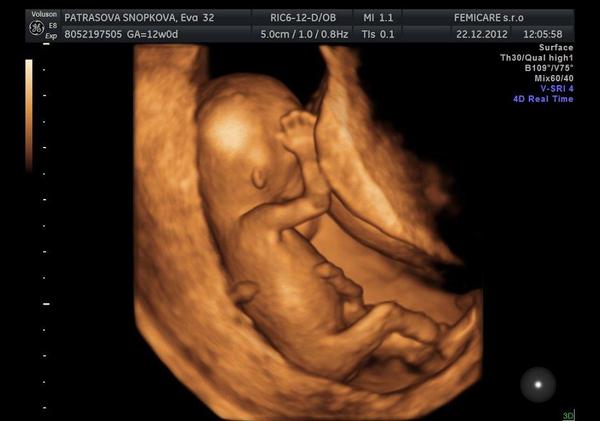

k kocky dodatocne prajem krasne sviatky boli aj krasne // vianoce @kikaneu tak gratulujem a pridavam foto nasho chlapceka

@michaelamia1902 gratulujem k synčekovi. su to nádherné zábery. to kde robia takéto?

@michaelamia1902 krásne bábätko, gratulujem 😵 vidím tam tie jeho rozmery, že do 5 cm, a vyzerá ako veľký 🙂